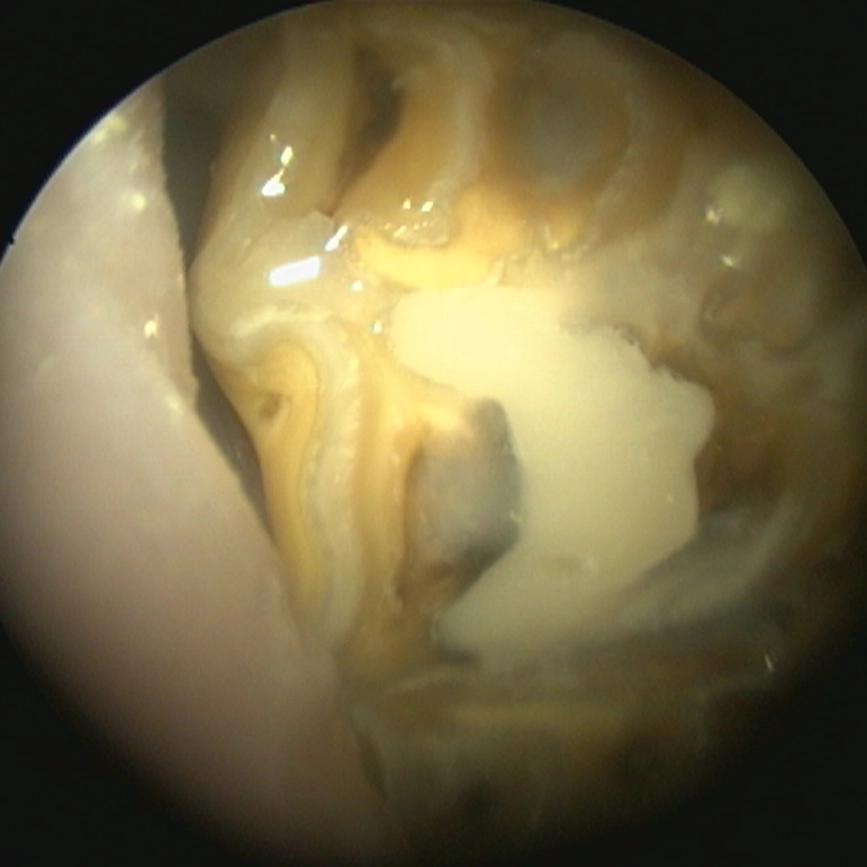

Cavity drilling